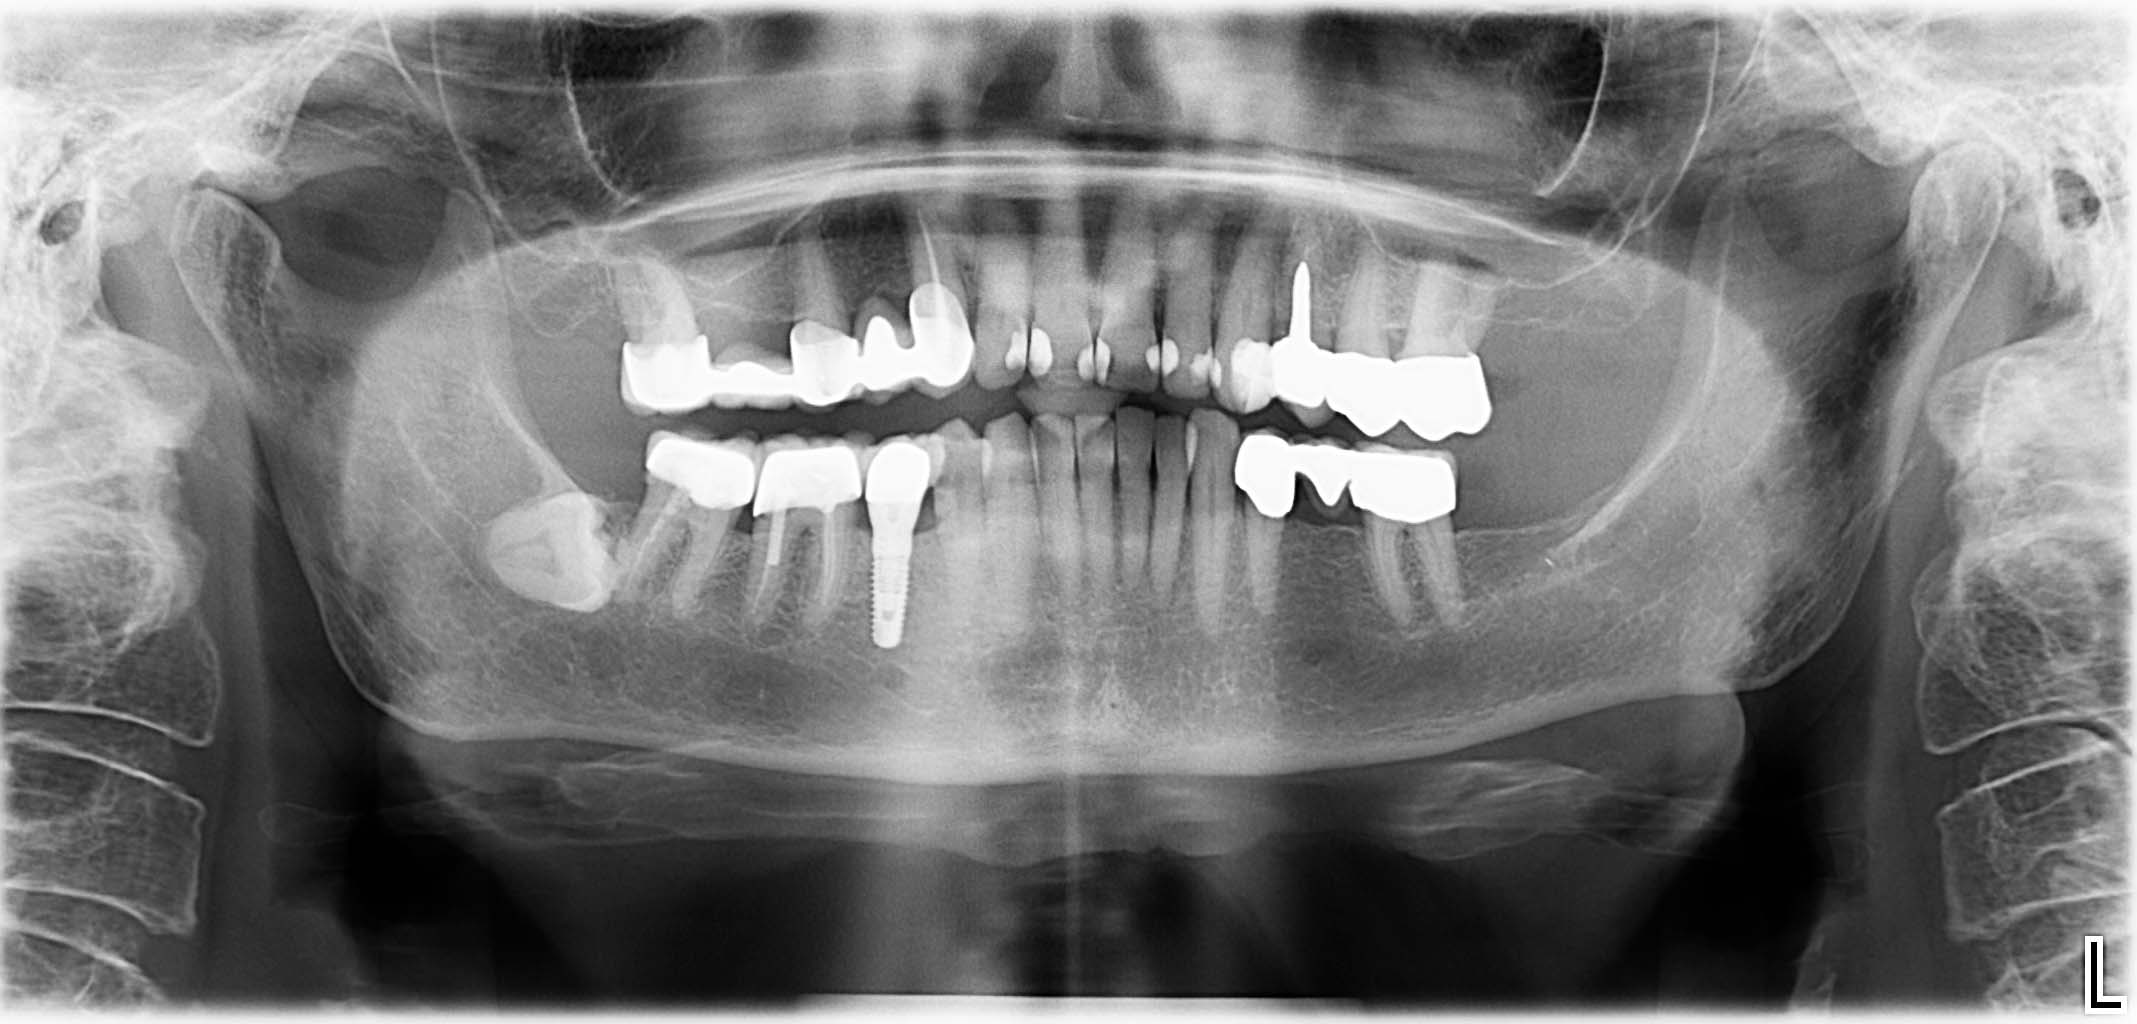

Erfolgreich implantierte Patientenfälle (klinische Fotos)